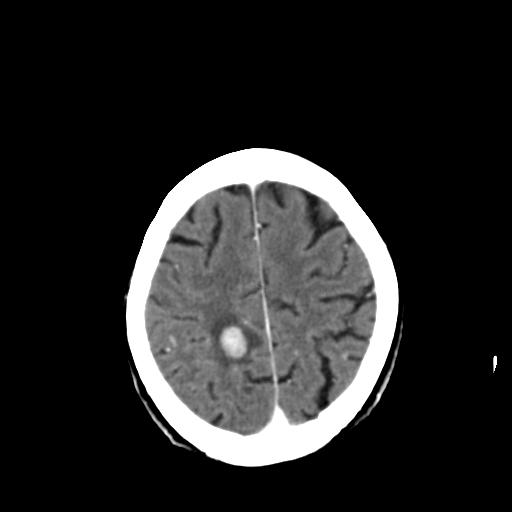

前两张头颅片子是平扫,请问能否考虑机化性肺炎或者间皮瘤?

本例颅内见多发大小不等高密度灶,有强化及水肿;另外,胸锁关节层面可能是第四胸椎及右侧肋骨起始部骨质欠连续,椎旁软组织肿胀,建议调骨窗观察。

右侧胸膜间皮瘤,双肺大泡,颅内多发转移(右顶叶、左侧侧脑室前角放射冠区)并出血。

左侧额叶及右顶叶实质内病灶首先应该考虑是转移性肿瘤伴出血{结合胸部强化}.

支持肺癌并脑内多发转移并出血;